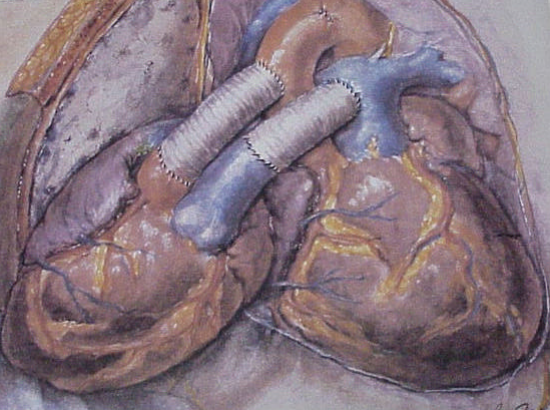

Um transplante cardíaco é uma operação em que um coração doente e falho é substituído por um coração doador saudável….